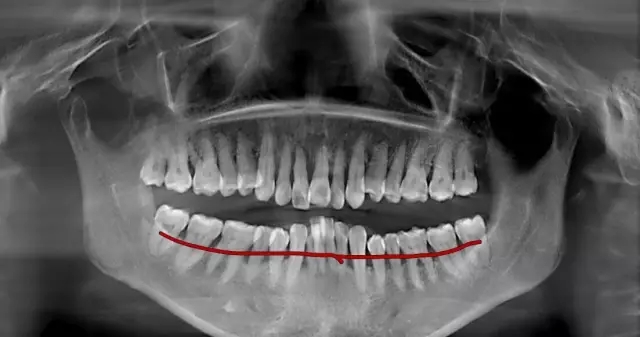

(圖中線條部位為正常牙齦位置,牙齒不光滑的表面布滿牙結(jié)石)

超聲波洗牙清潔掉牙齒表面上的菌斑和牙結(jié)石,牙齒根部的結(jié)石還未去除,且牙齦依然還會(huì)存在紅腫的情況,所以需要繼續(xù)齦下刮治治療。